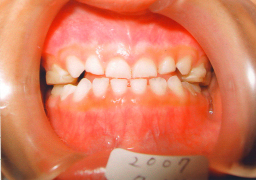

2007年 上顎乳臼歯(DE)にレジンで作った歯を接着剤で装着 咬合をあげることによって上顎骨の発達阻害を除去。 |